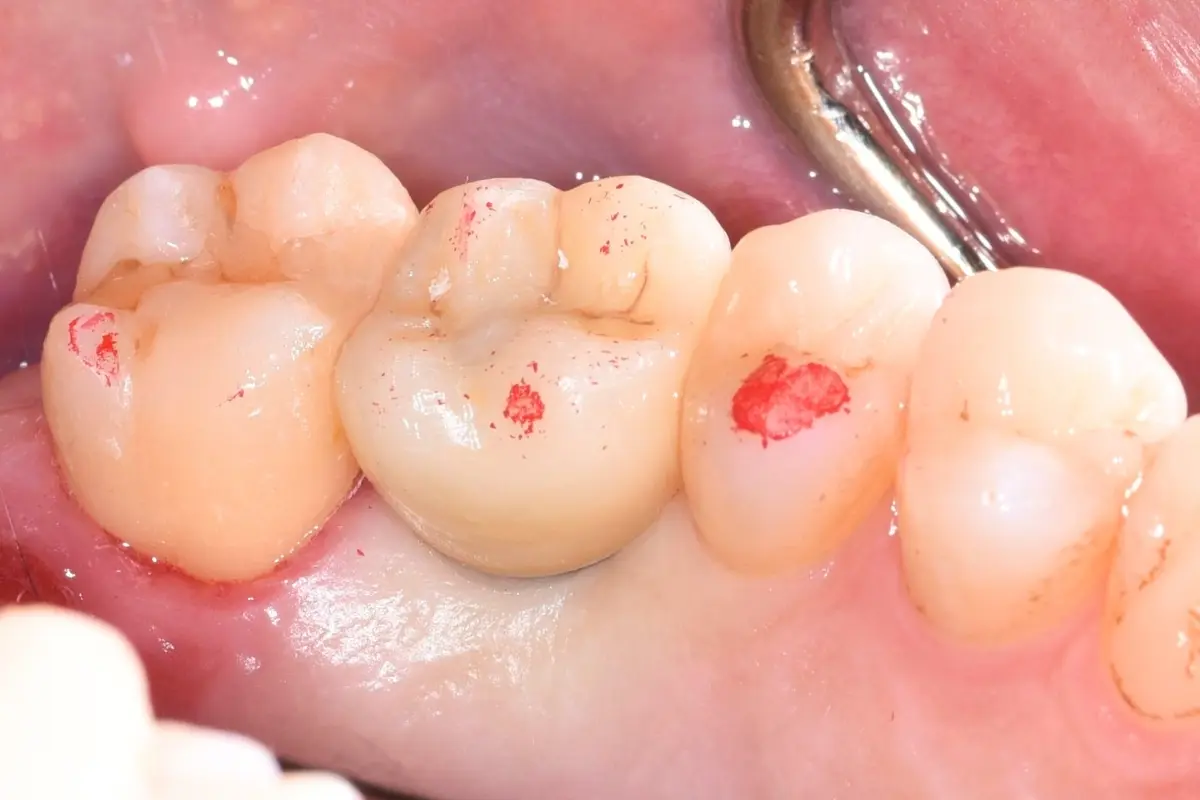

• 術前 12

術後 12

人工植牙

主治醫師

• 林明志

治療時間

約一年

主訴

左上假牙外側反覆長膿胞,想尋求治療方法